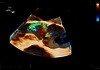

Conçue pour vous emmener plus loin, la nouvelle génération de cSound Pioneer se combine avec notre technologie de sonde avancée pour fournir des détails améliorés, un nouveau standard de flux couleurs et une incroyable imagerie 4D pour une confiance clinique dès le premier scan.